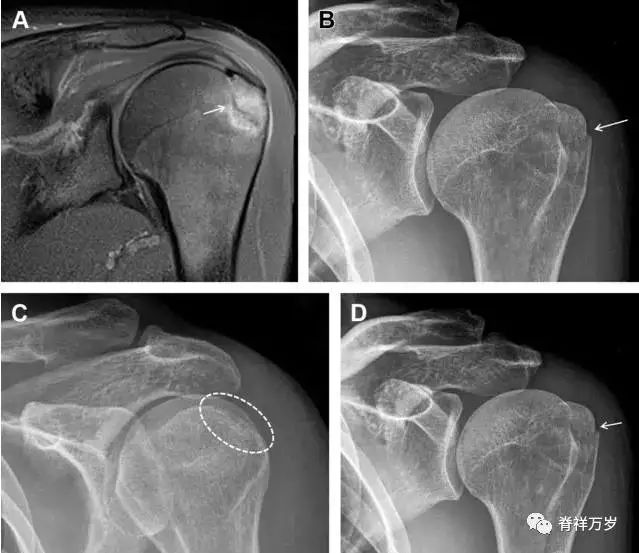

肩胛骨骨折

肩胛骨几何形状复杂,受到邻近其它骨性结重叠阻挡,且肩胛骨骨折少见,因此容易漏诊。当存在解剖变异时,诊断更为困难。

图 3 肩胛骨骨折正侧位片:由于骨块的叠加,(A)前后位片示「V」形高密度影(*),肩胛颈下方可见骨皮质碎片(箭头);(B)侧位片示骨皮质中断,骨折段移位,但由于肱骨的重叠遮挡,决断往往比较困难。

26

喙突骨折

喙突骨折可发生于直接*力暴**、肩关节脱位过程的肱骨头撞击、以及撕脱骨折(肱二头肌短头、喙肱肌)。

其中喙突基底部骨折最多见,常发生于直接*力暴**或肱骨头前脱位,骨折可延伸至关节盂。

而撕脱骨折多为喙突尖部的骨折。需要加拍腋位和 Stryker 位片(X 射线束以喙突为中心并头倾 10°,手臂外展,这样可以避开骨性结构的阻挡)。

有时,负重位片可发现并存的肩锁关节脱位,将有助于诊断。

图 4 喙突骨折。66 岁男性患者,猎枪射击后右肩前方疼痛。(A)内旋位前后位片投影隐约可见喙突基底部骨折(白色箭头),(B)外旋位前后位片投影结构存在重叠,(C)腋位投影时可良好显示。(D~F)喙突骨折伴 Hill-Sachs 损伤:肩关节脱位后慢性疼痛,喙突骨折块(*)向前外侧移位(双箭头),在外旋前后位(D)及腋位(E)片上均可显示,在内旋位前后位(F)片上,喙突被遮挡,但可见肱骨头 Hill-Sachs 损伤。(G、H)喙突骨折伴肩锁关节脱位,肩锁关节分离(白色双箭头),而喙锁间距正常(黑色的双箭头),应警惕喙突骨折。(I)喙突与肩峰骨化中心:对于未成年人,喙突与肩峰骨化中心可同时存在,易与骨折混淆,此时,拍对侧的 X 线片对比将有助于诊断。

27

肩峰骨折

肩峰骨折为高能量损伤,多由直接*力暴**导致,好发于中青年患者,多伴有肩关节其它结构损伤。有必要拍摄 Rockwood 位(前后位片,X 线束尾倾),特别有利于显示肩峰下部及肩峰下间隙。

图 5 肩峰骨折。内旋位前后位(A)片上,骨折线几乎被喙突完全遮挡, 但是在标准前后位(B)和腋位(C)片上可见骨折线。